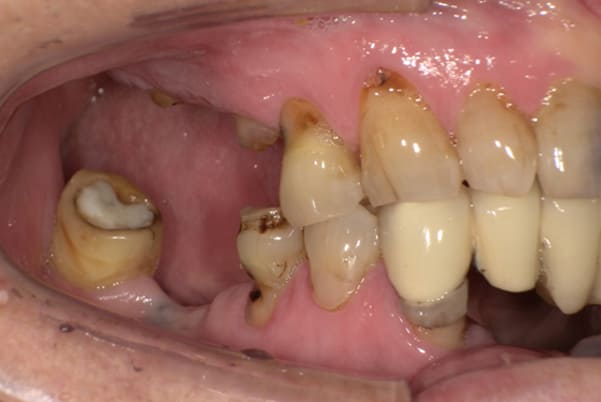

症例レポート[CASE.02]

入れ歯がカパカパして痛い、

歯がぐらぐらする

- 男性(60代)

- 入れ歯がカパカパする、歯がぐらぐらして痛い、食いしばれない

-

- 上顎精密総金属床総入れ歯

- 下顎精密金属床部分入れ歯

上の前歯が重度歯周病により動揺し、残せない状態のため、入れ歯も動揺がありました。

ご自身の歯に負担の少ないバネ、また見た目も改善

バネをかける歯は繋げることで強度を増し、歯への負担を軽減し、歯の寿命を長くする設計へ。

バネがかかる歯の被せ物は、歯への負担を減らし、入れ歯が動きにくいようになる形態をあらかじめ付与することで、より入れ歯の機能が高まります。

治療を行う際、被せ物や入れ歯は、別々に考えるのではなく、一口腔単位としてお口全体のことを考え最良の治療計画を立てることが歯の寿命、機能効果を向上させるため、専門医としてこのことは常に心掛けて治療を行っています。